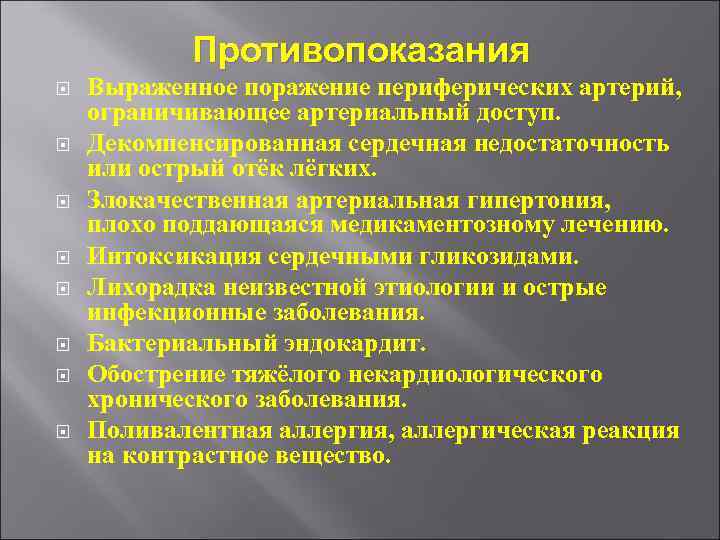

Противопоказания Выраженное поражение периферических артерий, ограничивающее артериальный доступ. Декомпенсированная сердечная недостаточность или острый отёк лёгких. Злокачественная артериальная гипертония, плохо поддающаяся медикаментозному лечению. Интоксикация сердечными гликозидами. Лихорадка неизвестной этиологии и острые инфекционные заболевания. Бактериальный эндокардит. Обострение тяжёлого некардиологического хронического заболевания. Поливалентная аллергия, аллергическая реакция на контрастное вещество.

Противопоказания Выраженное поражение периферических артерий, ограничивающее артериальный доступ. Декомпенсированная сердечная недостаточность или острый отёк лёгких. Злокачественная артериальная гипертония, плохо поддающаяся медикаментозному лечению. Интоксикация сердечными гликозидами. Лихорадка неизвестной этиологии и острые инфекционные заболевания. Бактериальный эндокардит. Обострение тяжёлого некардиологического хронического заболевания. Поливалентная аллергия, аллергическая реакция на контрастное вещество.